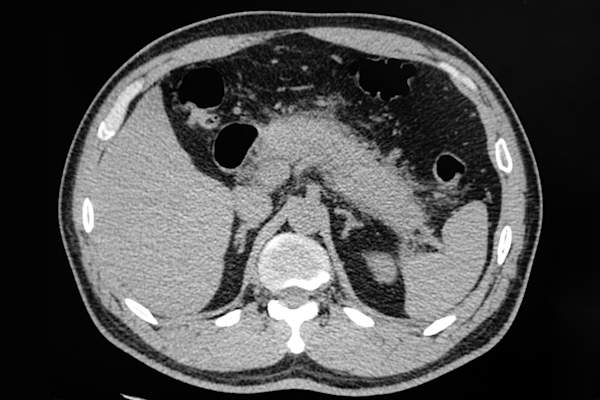

所以,你知道,你的肝脏甘油三酯做,但是当水平严重高般的约2000毫克/升,它也可以导致肝脏有害的脂肪堆积,或脂肪肝疾病,根据哈佛健康。脂肪肝可导致永久性一样肝损伤,肝硬化,这是当你的肝脏变得严重创伤严重的问题,使其难以发挥作用。